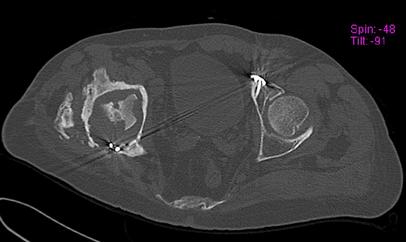

Пациент 49 лет, паровозная травма 23.2.2006, получил вертикальная

нестабильное повреждение таза, разрыв левого крестцово-подвздошного

сочленения, перелом лонной, седалищной костей слева, T-образный

оскольчатый перелом правой вертлужной впадины с переломом заднего

края, вывих правого бедра, посттравматическая пояснично-крестцовая

плексопатия с обеих сторон, паралич мышц правой голени.

В день травмы - вправление вывиха, скелетное вытяжение, 14.3.2006

чрескостный остеосинтез таза. 20.4.2006 остеосинтез правой вертлужной

впадины пластинами, осложнившийся нагноением межмышечной гематомы

правой ягодичной области. Получал консервативное лечение, было

достигнуто полное заживление раны. 24.7.2006 введены илиосакральные

винты слева. С декабря 2006 года и по настоящее время ходит на

костылях без опоры на правую ногу. Планируется THA. Помогите

определиться с вариантом костной пластики? И какую укрепляющую

конструкцию использовать?